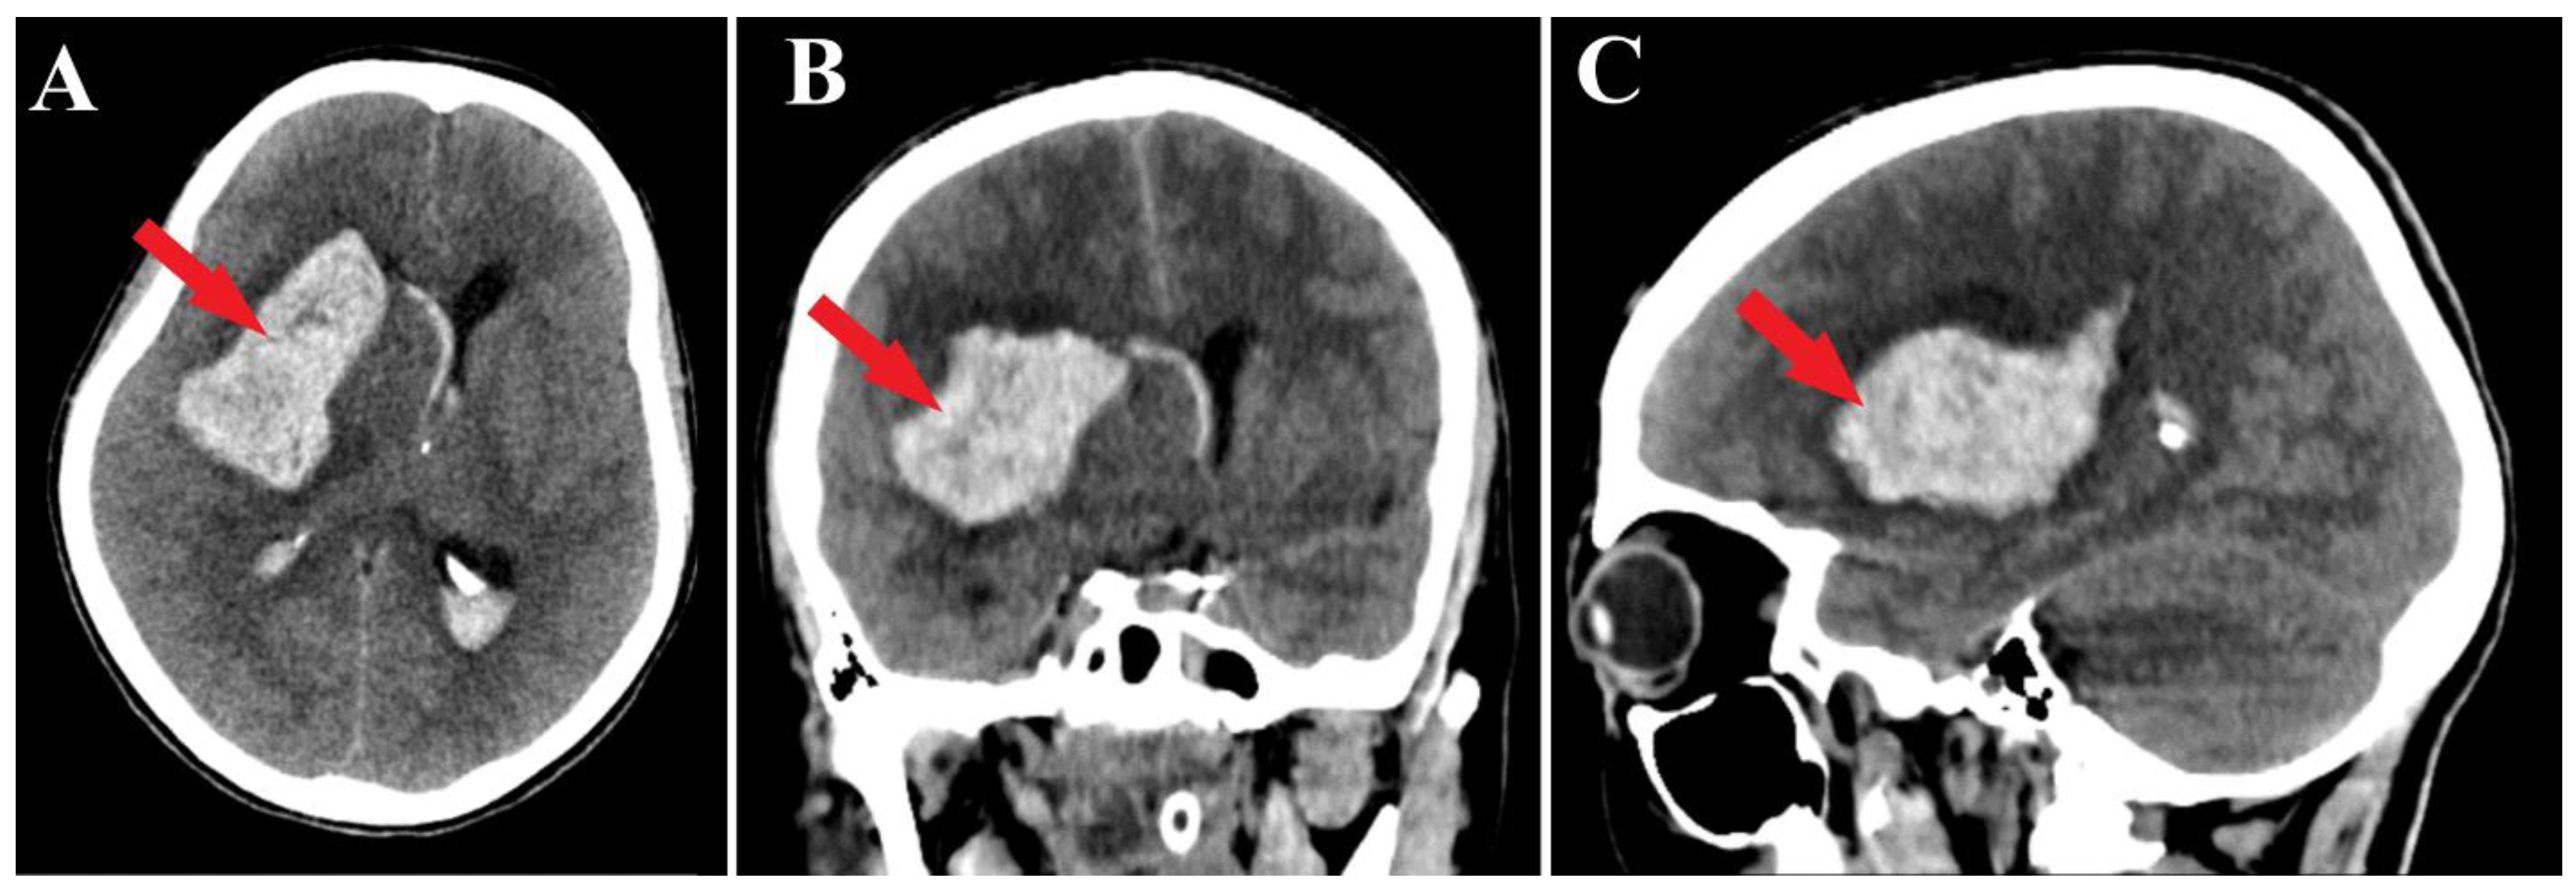

Figure 1.

Preoperative CT scan. Axial section (A) highlights the intraparenchymal hematoma (red arrow); moreover, frontal (B) and sagittal (C) sections depict the massive hematoma with panventricular implication too (red arrows).